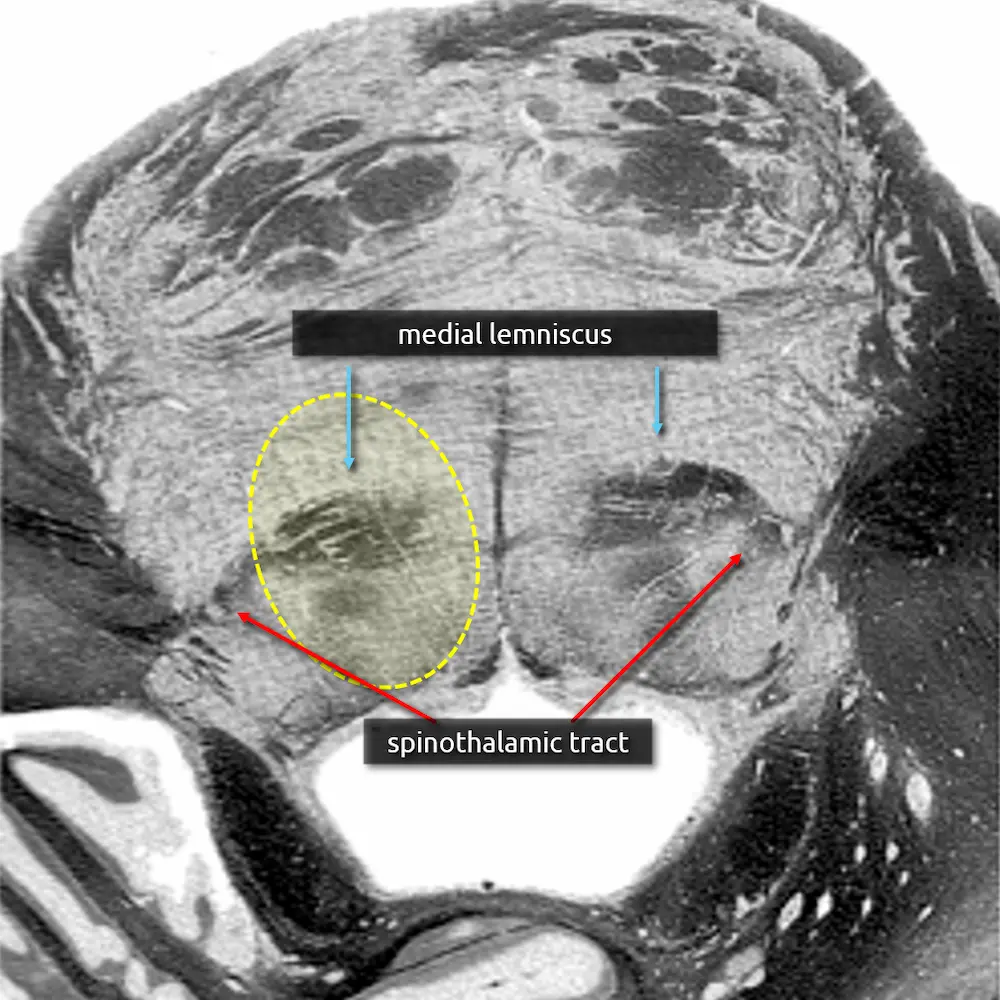

12. Spinothalamic tract

The spinothalamic tract is responsible for pain and temperature sensation. It is found throughout the dorsal brainstem adjacent to the medial lemniscus. Like the medial lemniscus, fibers terminate at the thalamic ventral posterolateral nucleus (VPL).

Fibers of the spinothalamic tract decussate in the spinal cord, so lesions will cause contralateral loss of pain and temperature sensation.

5. Medial lemniscus

The medial lemniscus is an ascending sensory pathway that spans the entire brainstem, originating at the nucleus gracilis and cuneatus (see level 5) in the medulla and ending at the primary sensory nucleus of the thalamus: the ventral posterolateral nucleus (VPL). It begins medially in the medulla and becomes more lateral at the level of the midbrain, located in close proximity to the substantia nigra. It is responsible for vibration sensation, fine touch, and proprioception.

Lesions involving the medial lemniscus may cause contralateral loss of vibration sensation and joint position sensation on physical exam with symptoms of numbness and paresthesias.